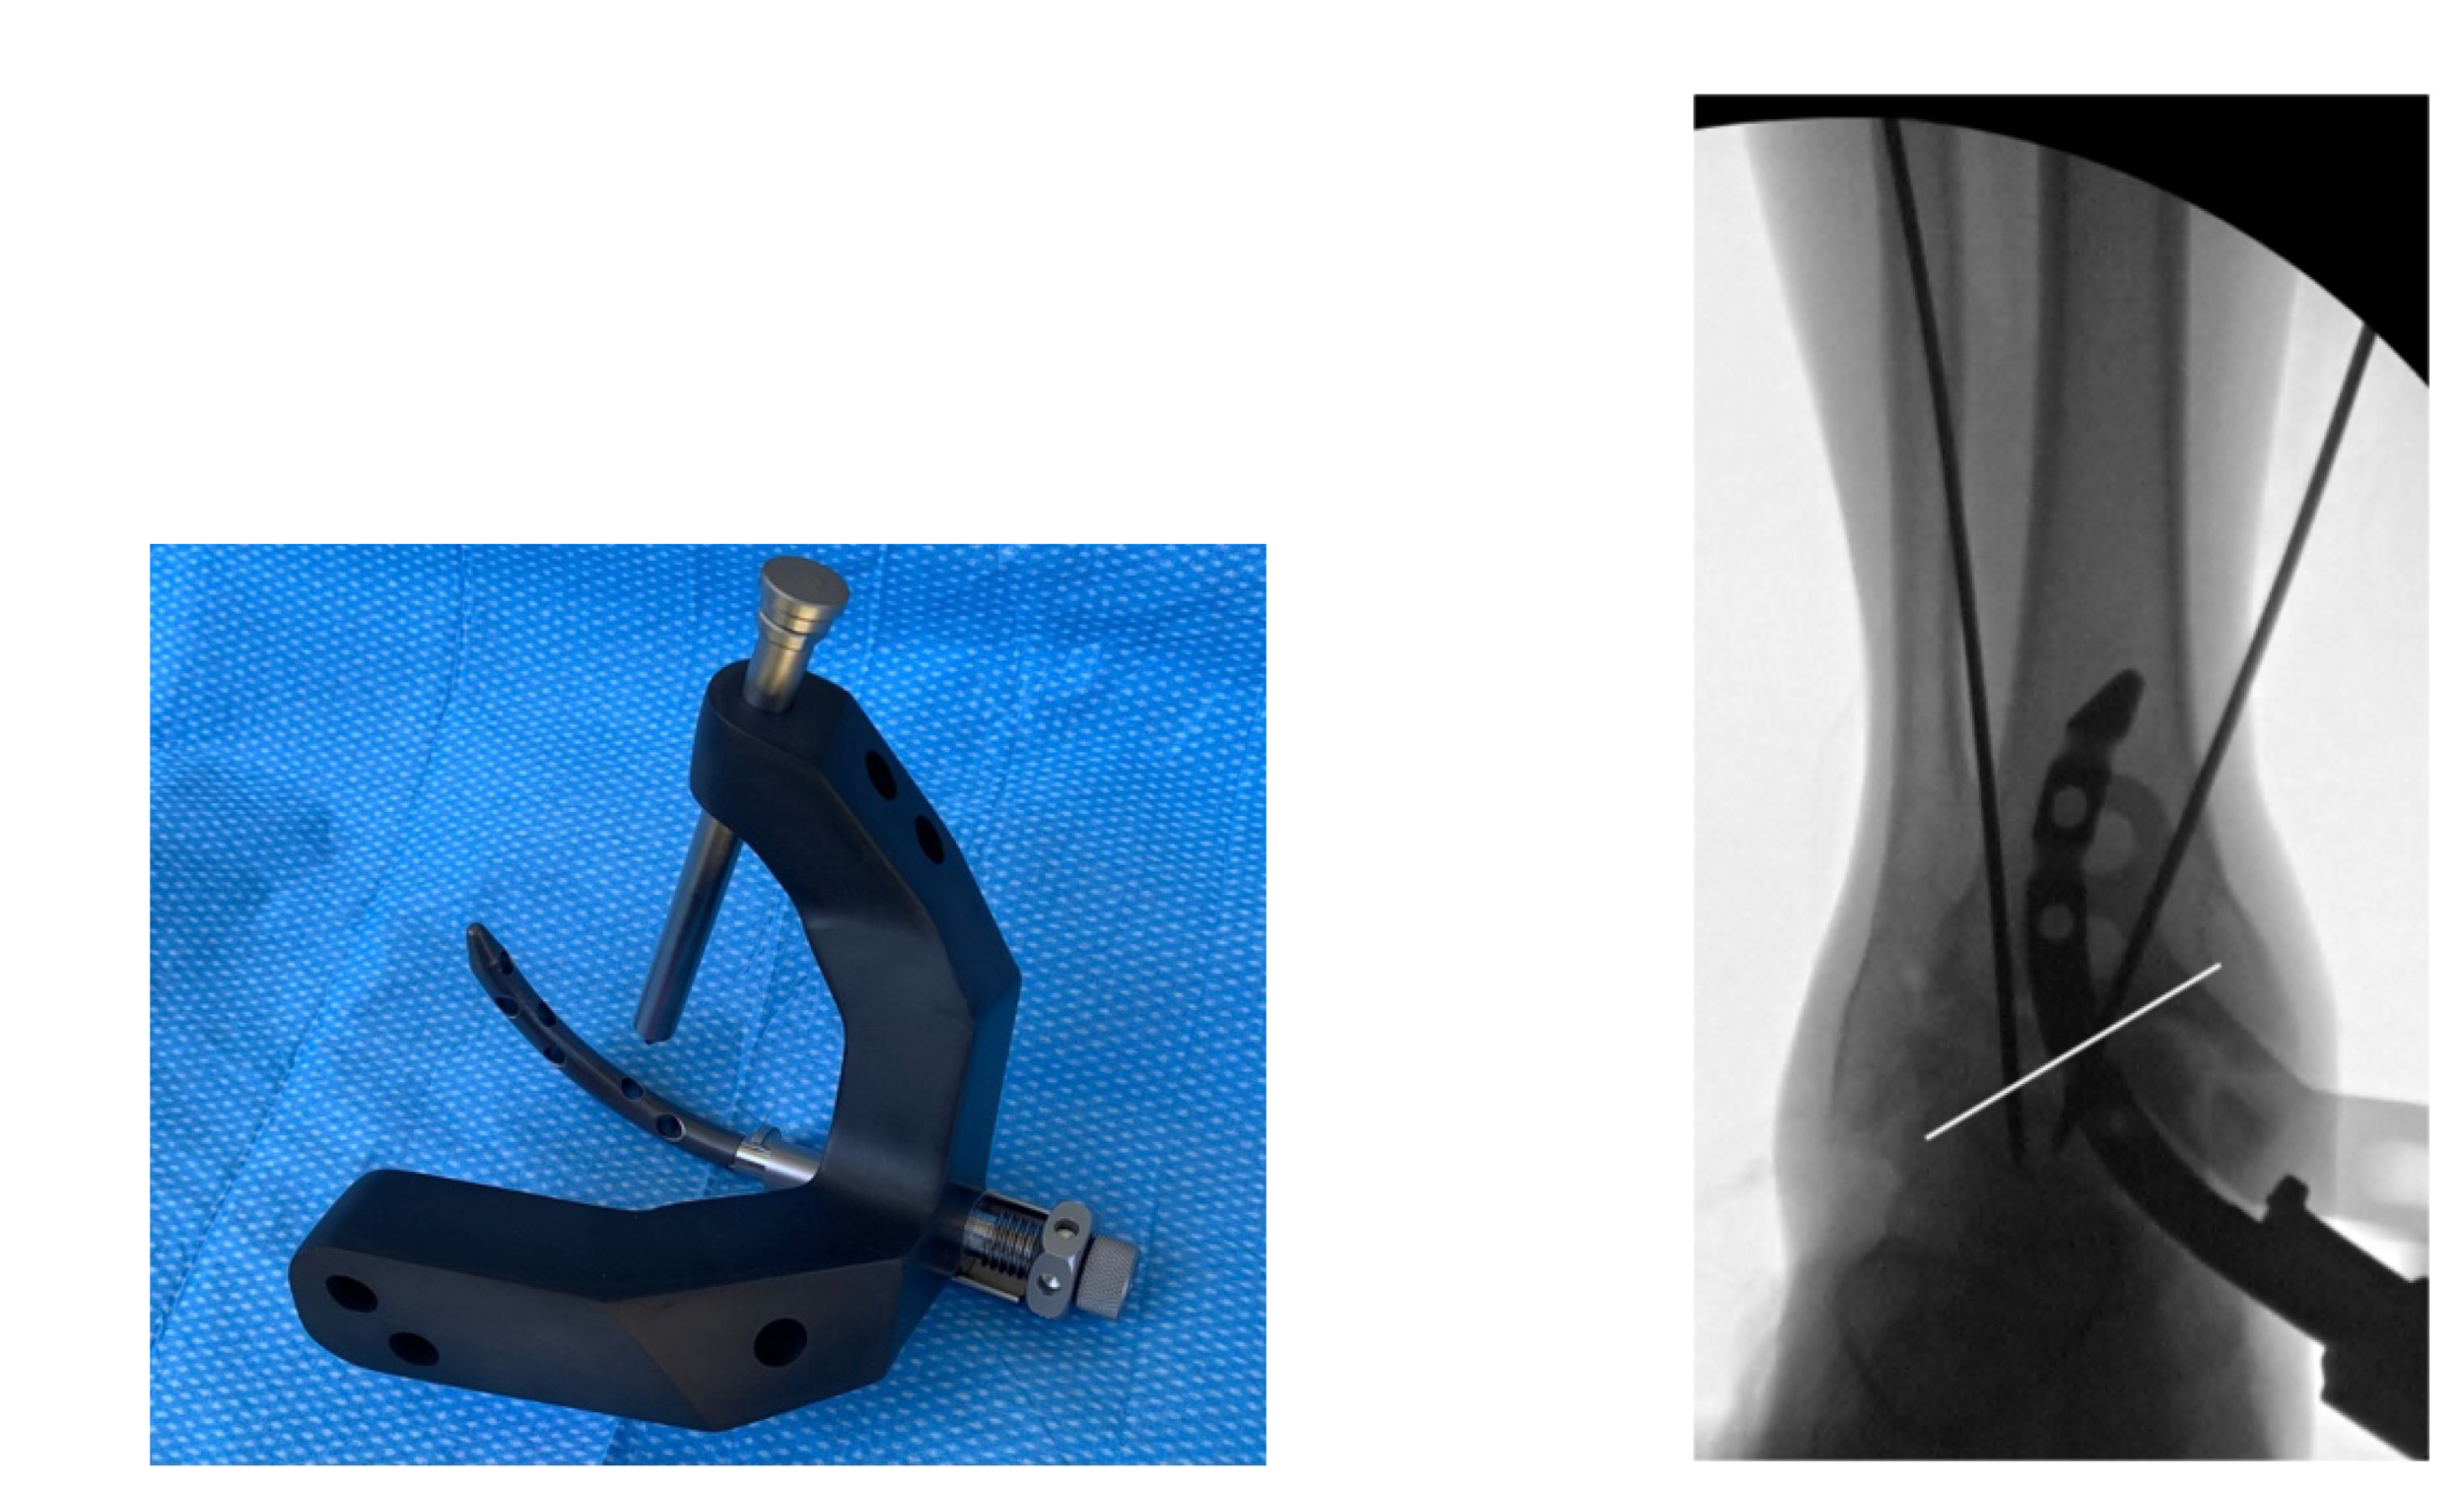

Entry portal: Using fluoroscopy, a straight entry awl is advanced while aiming superolateral and slightly posteriorly. The awl should exit slightly lateral to the center of the talar dome on the radiographic anterior-posterior view and parallel with the longitudinal axis of the tibia on the lateral view. Of note, a drill can alternatively be used for this step after an awl creates the entry portal at the insertion site [Figures 2A, 2B, and 2C].

- A mallet is used to advance a curved trocar through the talus across the joint line into the tibia, creating a curved pathway [Figure 3].

- An appropriately sized Shotel Nail attached to a drill guide is inserted while the nail depth is adjusted so that the transarticular screw trajectory is aimed toward the lateral process of the talus [Figures 5A and 5B].

._the_shotel_nail_on_locking_jig_with_cross-locking_trocar._b_(right)._intraoperat.png)